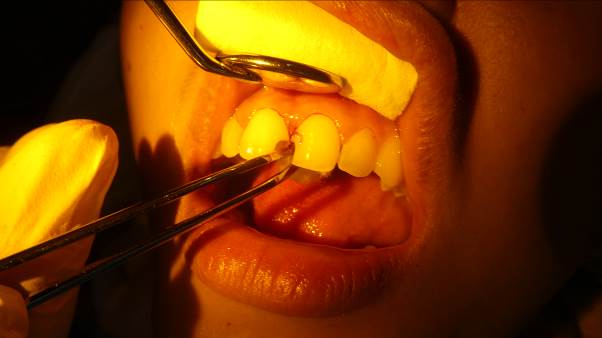

Carl S. and Friedrich K. came to us from August 11th to September 22nd. Both had studied dentistry in Ulm and now wanted to help the patients here at the clinic with their dental problems. Having worked together before, they quickly settled in. From the first day, the dental clinic was full. During their stay, an Apex device, which is needed for root canal treatment, arrived, and we ordered the digital X-ray machine mentioned in the last letter. This was a real benefit for the young dentists and was used quickly and frequently. Because it is digital, it offers the advantages of filmless image display, and we don't need X-ray films or developing solutions for this device. The initial investment was somewhat higher, but in the long run, there are many advantages. The young dentists also performed the first root canal treatment, so the Apex device was used immediately. Like the dentists before them, they also noticed the poor condition of the patients' teeth, which motivated them to work even more diligently and efficiently. They also trained the patients in good oral hygiene.

On October 8th, a new team of dentists arrived so that dental treatments could continue. Harun S., Alice F., Katharina G., and Anna H. They had studied dentistry at the University of Regensburg and now wanted to work full-time. Unfortunately, holidays and the local elections reduced the number of patients significantly. Alice F. had to leave after a few days because she became ill. More patients could have been treated, but for the population, their teeth were not a priority in October, unfortunately, because the need is still great.

On November 5, Marina G., Leandra D., and Julie K. (University of Giessen) arrived for two weeks to gain some practical experience. They were accompanied by Mr. Jelte G.-B., who has been practicing dentistry for some time. After his time in the Philippines, he plans to move to Osnabrück to learn more about surgical dentistry in an extensive practice. The three young dentists were happy to have him in the background when their patients required complex treatments.

The last guest to arrive was Nina W. from Freiburg. She had also gained experience in a dentist's office, so by the end of the year, with her and Mr. Jelte G.-B., we had an experienced team. They helped many patients at the dental clinic. Like all dentists, our two volunteers, Maria and Birgit, supported them and helped with patient admissions, translations, and instrument cleaning. In addition to the dental clinic, they helped us pack relief supplies after the flood disaster—I'll report on this later—got involved in youth work, and learned about the country and its culture. Both will travel further in the Philippines after their time with us.

In November, we moved our old dental unit to the elementary school so students could have regular checkups with our visiting dentists. We will also be conducting the fluoride prophylaxis program there in the future and will then schedule children who need treatment at the dental clinic. This "outpost" will bring many benefits, and we are pleased that the old dental chair is still being put to such good use. We want to thank the German Dental Aid Organization for its many years of support for our dental clinic.